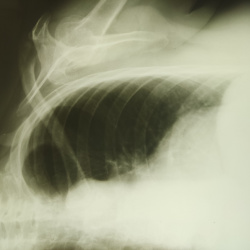

Женщина 45 лет. Как бы Вы описали ППН и как бы заключились?. Вижу в правой в/ч пазухе две доп тени.